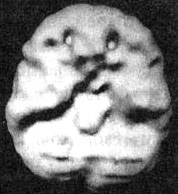

Раньше СДВ рассматривали как некоторое нарушение, имевшееся у гиперактивных мальчишек и компенсировавшееся по мере того, как они взрослели. Сегодня мы знаем, что многие, страдающие СДВ, с возрастом не избавляются от этих симптомов и что это нарушение часто встречается не только у представителей мужского пола, но и у девочек и женщин. По некоторым подсчетам, в США численность страдающих СДВ доходит до 17 млн человек. Кент Когда мы познакомились, ему было 24 года. Он обратился за помощью, так как к тому времени три года просидел на первом курсе колледжа. Он не мог сдать экзамены за первый курс. Он хотел поступать на медицинский факультет университета. Все говорили ему, что он «рехнулся»! Как он мог рассчитывать поступить на медицинский факультет, если был не в состоянии сдать экзамен за первый курс колледжа? Однако потом его мать прочла книгу под названием «Окна в сознание с СДВ» и подумала, не с этой ли проблемой столкнулся ее сын. Ознакомившись с историей болезни Кента, я понял, что мы имеем дело с врожденным и недиагностированным случаем СДВ. Еще в детском саду он не мог долго сидеть на месте; он был беспокойным, отвлекающимся, неорганизованным и потому за ним закрепилась репутация неудачника. Отец Кента предложил провести ему сканирование SPECT. Он хотел убедиться в том, что Кент не пытается найти очередной отговорки, которая объясняла бы отсутствие результатов. В состоянии покоя мозг Кента работал нормально. Однако как только Кент постарался сосредоточиться, префронтальная кора «отключилась». Получив результаты клинического исследования и SPECT, я назначил Кенту Adderall, лекарственный стимулятор для лечения симптомов СДВ. Результаты оказались блестящими. В течение следующего семестра он сдал все долги. Через полтора года получил диплом Associate of Arts (ученая степень, которая присваивается по завершении двухлетней программы обучения), а еще через три года получил степень бакалавра по биологии. Он поступил на медицинский факультет! Через несколько месяцев приема Adderall я сделал Кенту повторное сканирование SPECT. Как было видно на снимке, реакция на лечение была не просто положительной: после приема препарата активность его префронтальной коры заметно усилилась. Мозг Кента. СДВ. До и во время приема Adderall Трехмерное изображение — нижняя поверхность. ![]() В состоянии покоя — обратите внимание на хорошую активность всего мозга. ![]() Во время концентрации: обратите внимание на выраженное снижение активности в префронтальной коре (см. стрелки). ![]() При концентрации во время приема Adderall — обратите внимание на улучшившуюся активность в мозге в целом. Отношение к Кенту со стороны его отца потрясающе изменилось. Он сказал мне: «Я всегда думал, что он просто ленится. Так грустно думать, что все эти годы он был нездоров, а я просто ругал его за лень. Как же мне хотелось бы вернуть это время назад!» У меня был пациент, владевший 10 компаниями, — ему это было необходимо, чтобы оставаться «в тонусе». Когда мозг работает на «сниженных оборотах», человек чувствует себя некомфортно. Подсознательно такие люди стремятся «завести» свой мозг кофе или сигаретами (и то, и другое — мягкие стимуляторы), ссорами, гневом, быстрым темпом жизни или физической активностью с мощным стимулирующим эффектом, как, например, банджи-джампинг (любителям этого вида развлечений стоит пройти сканирование мозга по поводу СДВ!). СДВ в семье По мнению специалистов, на развитие многих психических нарушений большое влияние оказывает наследственность. Не является исключением и СДВ. Вот история болезни, прослеживающаяся в одной семье. Пол (20 лет) пришел ко мне на прием, так как не мог окончить учебу на последнем курсе колледжа. В классе ему было трудно писать контрольные работы, он не мог сконцентрироваться, а мотивация находилась на довольно низкой отметке. Он стал подумывать о том, чтобы бросить школу и идти работать вместе с отцом. При этом ему совсем не нравилась перспектива бросать учебу за несколько недель до выпуска. Пока я заполнял его историю болезни, Пол успел рассказать мне о том, что раньше у него случались приступы депрессии, которые ему лечили лекарством Prozac без особого успеха. Сканирование SPECT выявило повышенную активность лимбической области (связанную с депрессией) и пониженную активность ПК во время выполнения задания на концентрацию. Я назначил лечение антидепрессантами в сочетании с лекарственными стимуляторами. Результат оказался прекрасным. Он окончил колледж и получил работу, о которой мечтал. Увидев, как помогло лечение ее сыну, мать Пола Пэм пришла ко мне на прием сама. В детстве ей трудно давалось учение. Несмотря на то что она была очень артистичной, ей не особо хотелось учиться, и учителя поставили на ней крест. Уже став взрослой, Пэм вернулась к учебе и получила диплом учительницы начальных классов. Чтобы преподавать в средней школе, ей надо было сдать национальный экзамен для учителей. Все четыре попытки оказались неудачными. Пэм была готова отказаться от этой затеи и пойти учиться по другой специальности, но тут она увидела, как помогло лечение Полу. И тогда она подумала, что, может быть, и ей можно помочь. Ее результаты SPECT были сильно похожи на результаты Пола. Ей было назначено похожее лечение, и через четыре месяца она сдала свой экзамен. После того как в семье появилось два успешно пролеченных случая, Пэм привела ко мне девушку-тинейджера Карен. Как и ее брат, Карен была умным ребенком. Тем не менее ей плохо давалась учеба. К тому времени, как мы встретились, она жила в Лос-Анджелесе и занималась на факультете журналистики. Она жаловалась, что учебный материал для нее слишком труден. Она часто страдала от плохого настроения, беспокойства, легко отвлекалась, была импульсивна и вспыльчива. Несколько лет назад она лечилась от алкоголизма и привыкания к амфетамину. Она рассказала, что алкоголь снимал у нее беспокойство, а амфетамин помогал сосредоточиваться. Результаты SPECT-сканирования у Карен оказались похожи на результаты ее матери и брата. Как только она начала принимать лекарства, в ее состоянии произошли перемены, которым она была очень рада. В классе она могла спокойно сосредоточиться, а задания стала выполнять в два раза быстрее. Уверенность в собственных силах укрепилась настолько, что Карен стала искать работу ведущей в телепрограмме. Раньше ей это даже не пришло бы в голову. Из всех членов семьи с самым сильным нежеланием пришел ко мне их отец — Тим. Он упирался, несмотря на то что и Пол, и Пэм, и Карен говорили ему, что он должен пойти. Он говорил: «Со мной все нормально. Посмотрите, какого успеха я сумел добиться!» Однако в его семье знали и другое. Несмотря на то что Тиму на самом деле принадлежал продуктовый магазин, сам он был замкнутым и отстраненным. Он быстро уставал, легко отвлекался и был довольно разбросанным в работе. Успеха в бизнесе он добился во многом благодаря сильной команде сотрудников, которые и занимались реализацией его идей. Ему было трудно учиться новым играм, например карточным, поэтому он стремился избегать каких-то встреч и общественных мероприятий. Тиму нравились острые ощущения. Например, несмотря на то что ему было уже 45 лет, он любил кататься на мотоцикле. В школе, в последних классах он учился плохо. Несмотря на высокий IQ, с трудом окончил колледж. Он менял одну работу за другой, пока не скопил достаточно денег на то, чтобы купить продуктовый магазин. В конце концов Пэм удалось уговорить Тима пойти ко мне на прием. Сама она уже собиралась с ним разводиться, так как была убеждена, что он ее не любит. Позже он рассказывал мне, что тогда чувствовал себя совершенно опустошенным и эмоционально, и физически, чтобы проводить с ней значительную часть времени. |